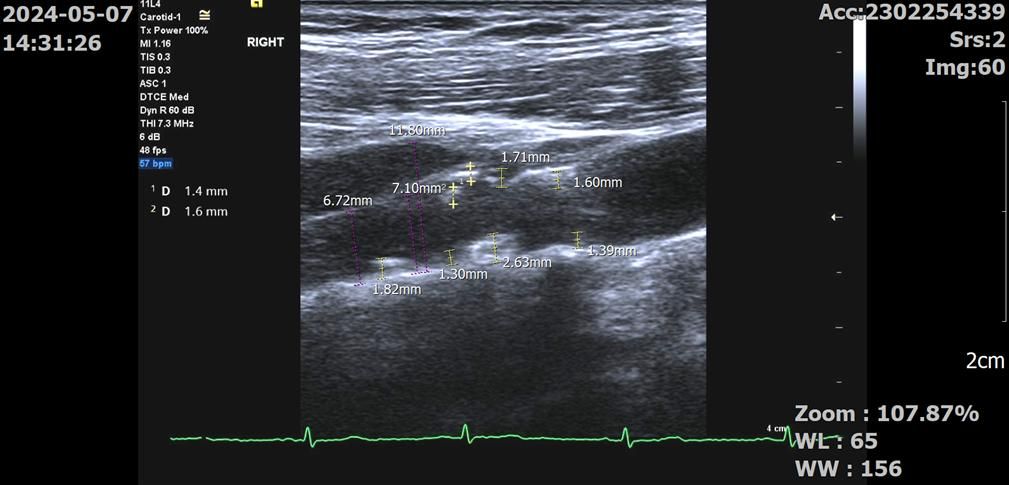

우측 bulb 및 ICA입니다. 병원에서 측정해주신 플라크는

ICA: 1.3, 1.6, 1.4mm

bulb: 2.8, 1.7, 1.6, 1.4mm 입니다.

우측 경동맥 내경 또한 어떻게 보는 것인지 몰라서 세 군데 재봤습니다.